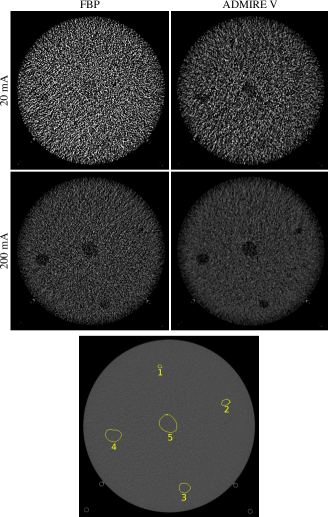

Finally, Figure 4 depicts the background images including virtual lesions of different areas, those correspond to circles with diameters of 4, 8, 12, 16 and 20 mm.

Refer to caption

Figure 4: Virtual lesion with various areas to the background images measured with tube currents of 20 and 200 mA and reconstructed by FBP and the ADMIRE level V. The contours of the lesions are shown in the lower figures.

The lesion-free images were obtained by tube currents of 20 and 200 mA. While at the middle of image measured by the tube current of 20 mA and reconstructed with FBP the lesion with largest area (lesion 5) can be presumed, in the image measured by the same radiation dose and reconstructed with ADMIRE V the lesions 4 and 5 can be seen. In the image measured by the tube current of 200 mA and reconstructed by FBP the lesions 3, 4 and 5 can be observed. Expect to the lesion 1, other lesions in the image measured by the tube current of 200 mA and reconstructed by ADMIRE 5 can be easily founded. SSIMLsubscriptSSIML\mathrm{SSIM_{L}} as a function of the lesion diameter and ADMIRE is plotted in Figure 5 and listed in the Table 5, s. Appendix.